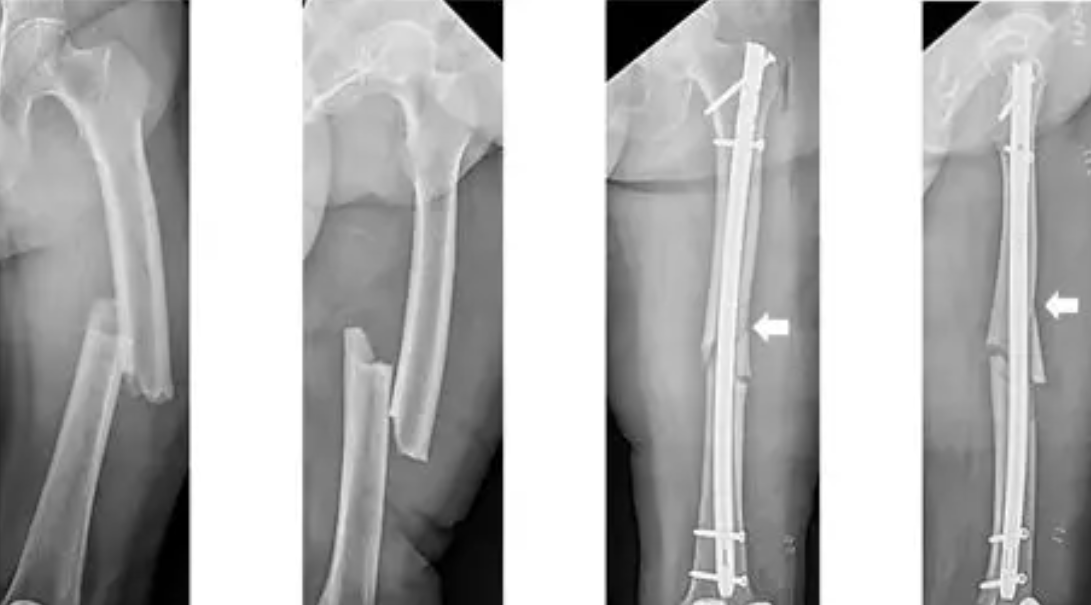

How is Orthopaedic Fracture Fixation Performed?

The broken bone is aligned and fixed with metal implants that hold it until it heals naturally.

- Proper bone healing

- Early movement and faster return to work

- Prevents deformity and stiffness

Recovery Timeline

Most bones heal in 6–12 weeks.